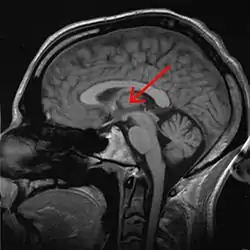

Thalamus marked (MRI cross-section)

The thalamus (pl.: thalami; from Greek θάλαμος, "chamber")[1] is a large mass of gray matter located in the dorsal part of the diencephalon (a division of the forebrain). Nerve fibers project out of the thalamus to the cerebral cortex in all directions, known as the thalamocortical radiations, allowing hub-like exchanges of information. It has several functions, such as the relaying of sensory signals, including motor signals to the cerebral cortex[2][3] and the regulation of consciousness, sleep, and alertness.[4]

Anatomy

The thalamus is a paired structure of gray matter about four centimetres long, located in the forebrain which is superior to the midbrain, near the center of the brain with nerve fibers projecting out to the cerebral cortex in all directions. The medial surface of the thalamus constitutes the upper part of the lateral wall of the third ventricle, and is connected to the corresponding surface of the opposite thalamus by a flattened gray band, the interthalamic adhesion. The lateral part of the thalamus is the phylogenetically newest part of the thalamus (neothalamus), and includes the lateral nuclei, the pulvinar and the medial and lateral geniculate nuclei.[6][7] There are areas of white matter in the thalamus including the stratum zonale that covers the dorsal surface and the external and internal medullary laminae. The external lamina covers the lateral surface and the internal lamina divides the nuclei into anterior, medial, and lateral groups.[8]